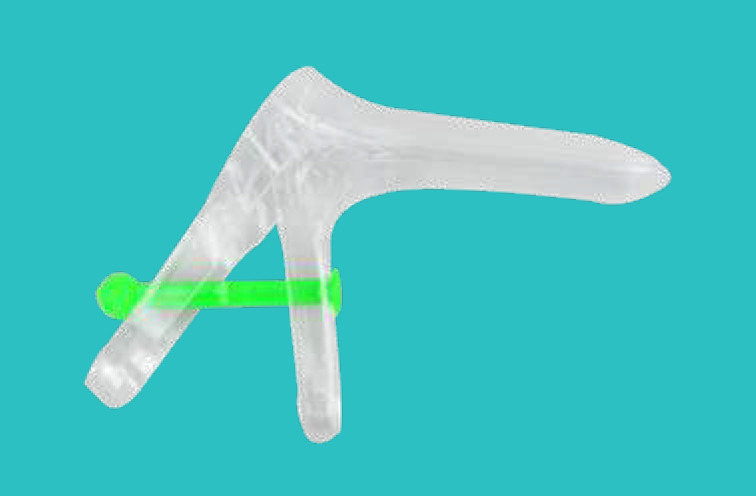

Vaginal Speculum

Description: It can be used for the checking and treatment of gynecology disease in hospitals or clinics. Before using it, user must read the usage manual, and then take the speculum, push the “duckbill” of speculum that is closed into the vaginal slowly.

Open the “duckbill” of speculum according to demand, fix the nut of speculum, then it can be used for checking and treatment of gynecology disease. After all, loose the nut of speculum, and take “duckbill” of speculum out of the vaginal slowly.

Specification:

Material: Polystyrene, transparent substance, non-toxic, medical grade.

Size: Large, Medium, Small.

Sterilization: EO.

Packing: Steriled in individual polybag or Film+Polybag or Blister pack, 100pcs/ctn.

Carton Size: 520x380x360mm G.W: 7kgs N.W: 6kgs

Disposable Vaginal Speculum With Side Screw

Disposable Vaginal Speculum French Type

Disposable Vaginal Speculum Spanish Type

Disposable Vaginal Speculum With Middle Screw

Disposable Vaginal Speculum Australia Type

Disposable Vaginal Speculum South Asian Type